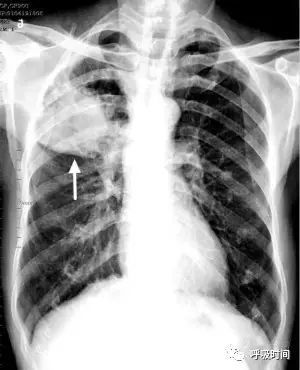

图片

图 21:女,40 岁,咳嗽发热 3d 前来就诊。

原诊断:左上肺结核(白箭头)并淋巴结肿大(黄箭头)。

审报告发现,左上肺阴影向外上软组织内延伸,且肺门部结节为(头绳上的)纽扣